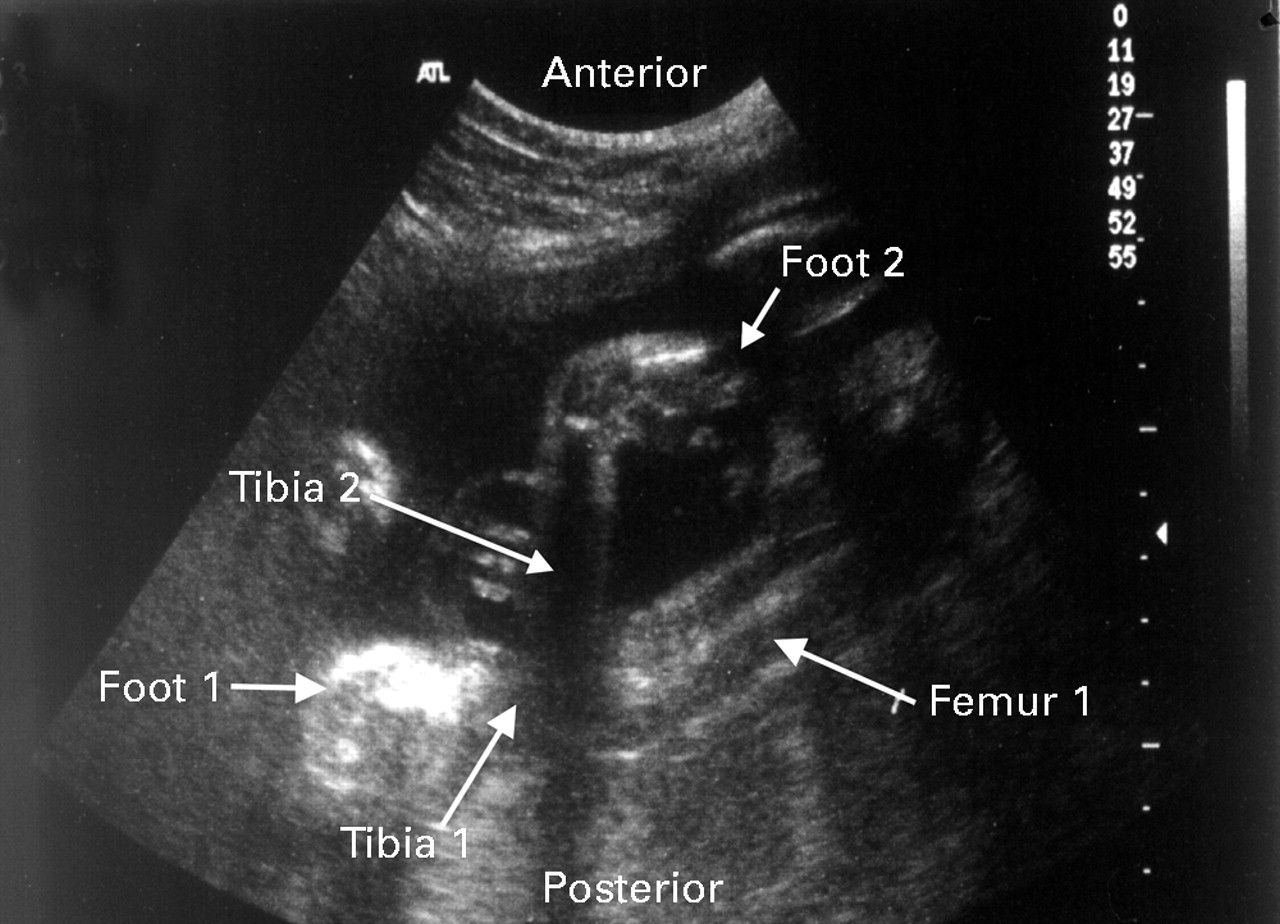

Club Foot Ultrasound Foot Anatomy Ultrasound The structures of the ankle and hindfoot are superficial and ideally suited for sonographic evaluation. Ultrasound anatomy of the ankle and foot. The stabilising ligaments of the lateral. Ultrasound examination of the ankle and foot is comfortably completed with the patient supine and the foot and ankle on the examination. • less common specific indications: Ultrasound is a valuable diagnostic. Foot Anatomy Ultrasound.

Club Foot Ultrasound Foot Anatomy Ultrasound On a prone position, let the foot hanging out of the examination table. The stabilising ligaments of the lateral. Ultrasound is used for the soft tissue structures of the foot. Ultrasound anatomy of the ankle and foot. Musculoskeletal ultrasound (us) is a rapidly evolving technique that is gaining popularity for. Ultrasound is a valuable diagnostic tool in assessing the. Suspected. Foot Anatomy Ultrasound.